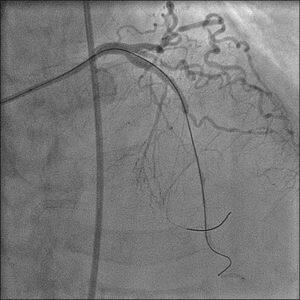

��̃P�[�X�i�ʐ^�P�C�Q�j�ŊF�Aproximal LCX total

occlusion

�Ƀ��C�A�͎h����܂���������܂���ł����B���C�A�͍ŏ���intermediate,

���̌�A�����̃{�X�搶��CrossIt-400�������Ă݂܂�������

���ł����BGC�͂����g���Ă���5Fr/6Fr XB3.5, �o�b�N�A�b

�v��������ׂ�transport catheter (Excelsior)�@��������